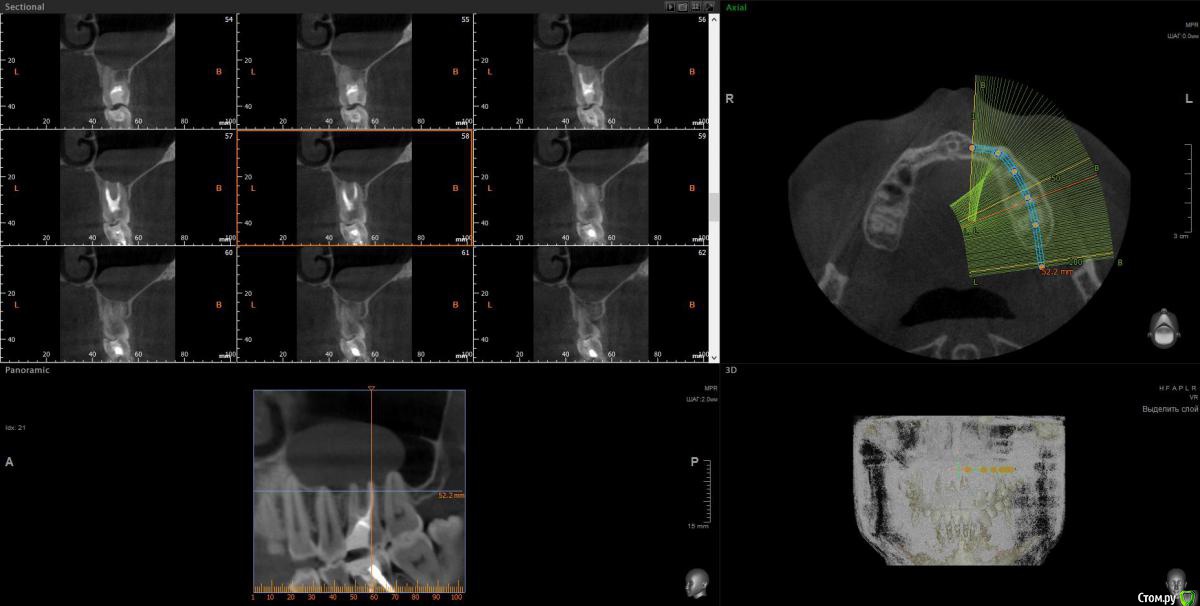

wladdX Опубликовано 13 декабря, 2016 Поделиться Опубликовано 13 декабря, 2016 Несколько скриншотов. Ссылка на комментарий

Гарриевич Опубликовано 12 декабря, 2016 Поделиться Опубликовано 12 декабря, 2016 Начните с лечения 6 зуба, так как по Кт он является возможной причиной процесса Ссылка на комментарий

red_butler Опубликовано 13 декабря, 2016 Поделиться Опубликовано 13 декабря, 2016 Лор назначает консервативное лечение с целью снятия обострения, лечите зуб и диспансерно наблюдаетесь. 1 Ссылка на комментарий